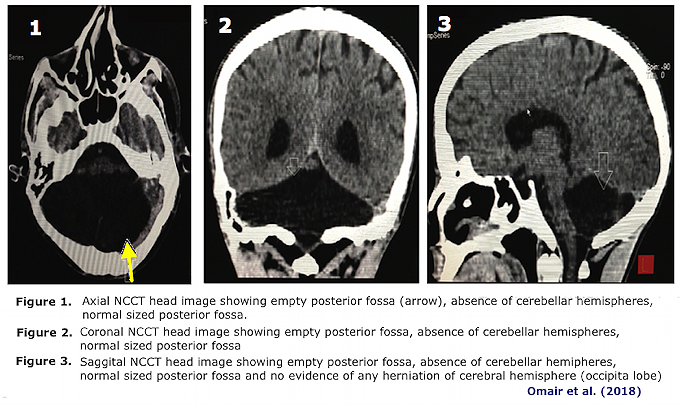

3. Indian Man, 45, Found to Lack Cerebellum (2018)

- A 45-year-old man in India who had a head injury was found to lack any cerebellum in a CT scan after his accident.

- Neurologists reported that his "birth was by a normal vaginal delivery. There was no history of any difficulty in walking or in carrying out routine daily activities. The clinical and neurological examination revealed no motor impairment. No evidence of ataxia [loss of muscle control & balance], dysarthria [inability to speak clearly because of muscle weakness], nystagmus [repetitive & rapid eye movements to the side], or intention tremor [shaking of the arm/hands in reaching toward an object] was noted. The Romberg’s test [inability to maintain balance because of loss of proprioception] was negative and deep tendon reflexes were normal" (Omair et al., 2018; emphasis & descriptors within brackets [] added")

Omair … (2018) Primary cerebellar agenesis in a normal man. Neurology India, 66, 871-873. https://doi.org/10.4103/0028‑3886.232287